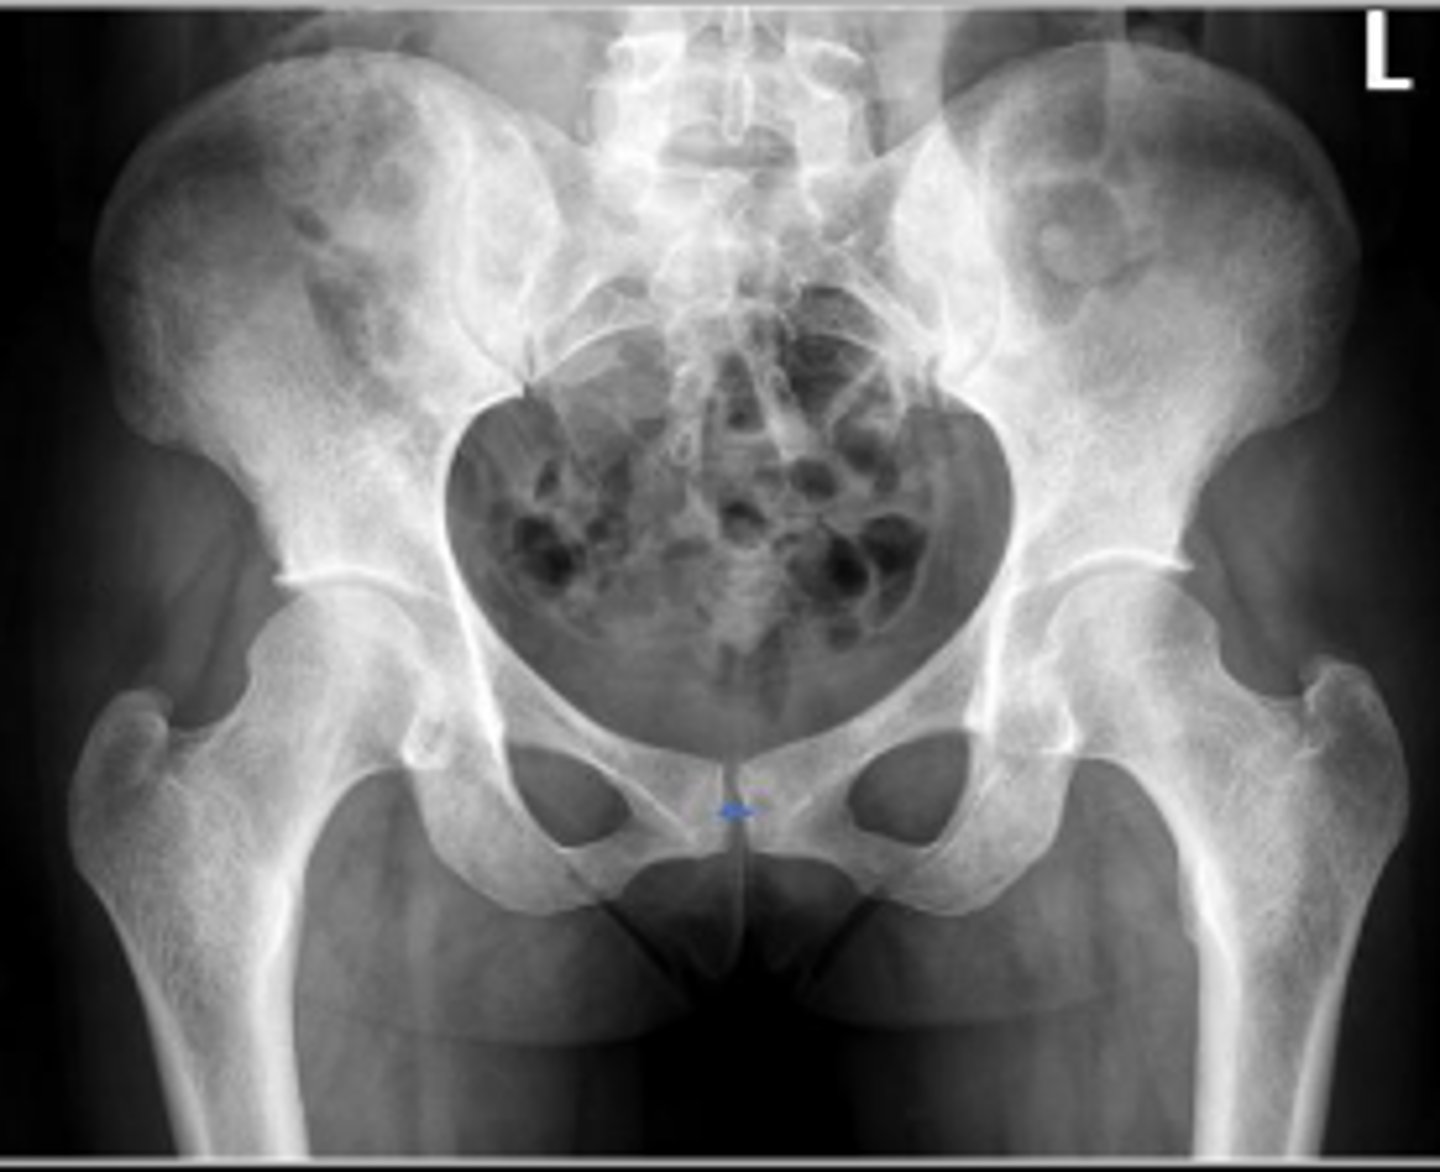

AP pelvis or bilateral hips

What is the name of the radiographic view?

10-15 degrees

How many degrees of internal rotation of the lower extremities is required for this view?

Iliac crest

What are the arrows pointing to?

Sacrum

What is the anatomical structure in between the lines?

ASIS

Left ischial spine

Sigmoid colon

What is outlined?

Right sacroiliac joint

What joint space are the arrows pointing to?

Pubic symphysis

What joint space is the arrow pointing to?